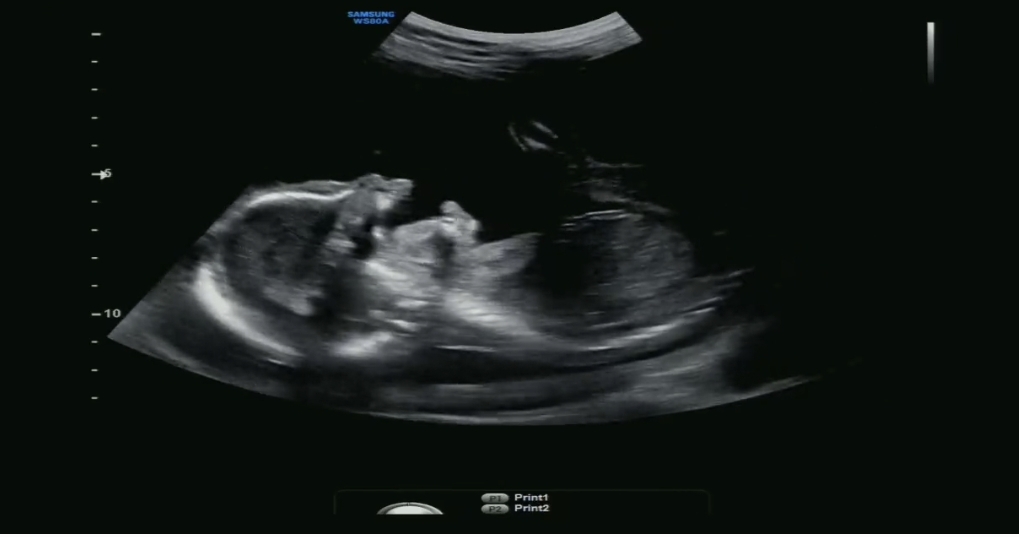

정밀초음파 하품하는 아기 포착

정밀초음파 보는데 아가가 뱃속에서 눈 비비고 하품하고 다 하고있더라구요 ㅎㅎ 운좋게 화면에 잡혀서 영상만 몇번씩 돌려보고있습니다 여러분들도 초음파에서 귀여운장면 많이많이 포착하시길바라며...!